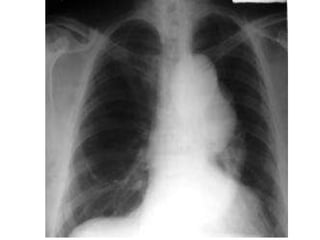

•    X-ray

• Chest x-ray